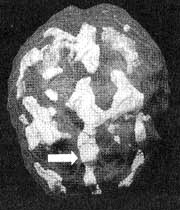

Мозг Роба. Результаты сканирования SPECT

Трехмерное изображение — активный мозг, вид сбоку.

До лечения: обратите внимание на выраженное усиление активности в поясной системе (см. стрелку).

После трех лет неуклонного улучшения состояния на фоне приема Anafranil (оба раза, когда предпринимались попытки снизить дозу, симптомы возвращались), повторное сканирование показало нормализацию функции мозга.